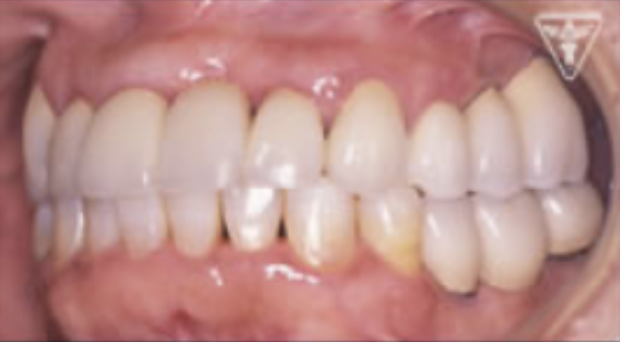

治療後